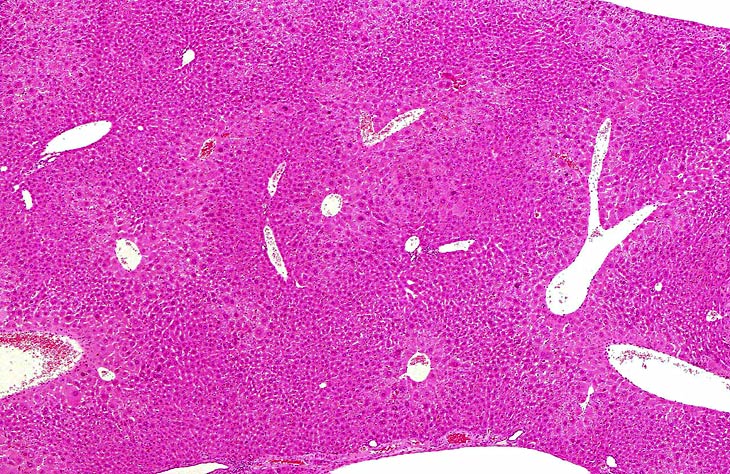

Centrilobular hepatocellular hypertrophy in a CD-1 mouse.

Centrilobular hepatocytomegaly (hypertrophy) in a mouse given phenobarbital for 8 months. Note the prominent eosinophilic cytoplasm reflective of smooth endoplasmic reticulum proliferation.